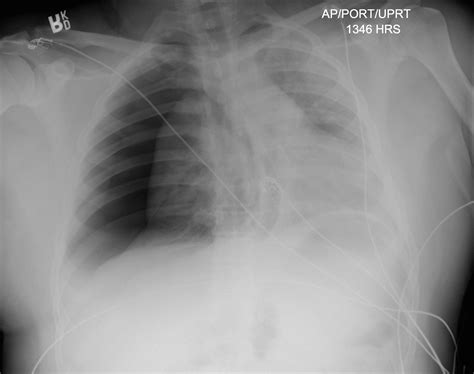

Case Study 1: A 35-year-old male presents to the emergency department after a high-speed motor vehicle accident. He complains of severe chest pain and shortness of breath. On examination, he is tachycardic, hypotensive, and has decreased breath sounds on the right side. A chest X-ray confirms the presence of a tension pneumothorax. The emergency physician performs needle decompression, and the patient's symptoms improve significantly. A chest tube is inserted shortly thereafter, and the patient is admitted to the intensive care unit for further management.